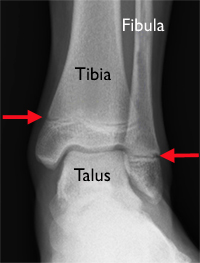

Złamanie kostki to bardzo częsty uraz wśród dzieci i dotyczy uszkodzenia 1 lub więcej kości w obrębie stawu. Zazwyczaj dotyczy to kości piszczelowej i strzałkowej, rzadziej skokowej. Najczęściej, do złamania dochodzi w obrębie płytki wzrostowej kości piszczelowej i strzałkowej. Chrząstka wzrostowa, inaczej zwana nasadową, to tkanka chrzestna znajdująca się w pobliżu zakończeń kości. Posiada ona liczne punkty kostnienia, które z tkanki chrzęstnej przekształcają się w kość. To właśnie chrząstka wzrostowa odpowiada za wzrost kości na długość oraz kształt jaki przyjmie ona w życiu dorosłym.Jest ona ostatnią częścią kości, która ulega twardnieniu. Z tego powodu, jest również najbardziej podatna na wszelkie urazy. Nawet najmniejszy ruch skrętny stawu skokowego u dziecka, może powodować poważne złamanie kości w obrębie stawu skokowego.

Siła skrętna działająca na stopę, zazwyczaj powoduje złamanie w obrębie kostki, a także zerwanie bądź naderwanie więzadeł i uszkodzenie torebki stawowej.

Reproduced and modified with permission from The Body Almanac. © American Academy of Orthopaedic Surgeons, 2003.